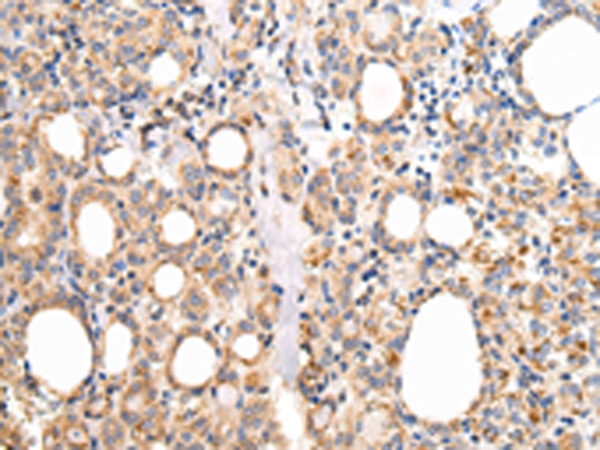

分类: 科研抗体货号: P08938别名: UCH-L3应用: WB,IHC反应种属: Human, Mouse, Rat